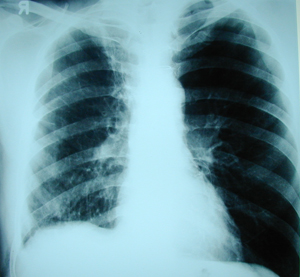

Εικόνα 1

Οπισθιοπροσθία ακτινογραφία θώρακος, που δείχνει σχεδόν oλικό πνευμοθώρακα στο δεξιό ημιθωράκιο που παρεκτοπίζει το μεσοθωράκιο προς την υγιή πλευρά.